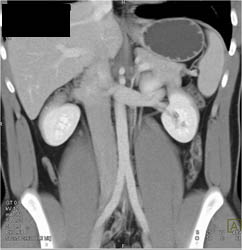

2 Renal Arteries and 2 Renal Veins With Lower Vein Surrounding Artery- VRT/MIPs. See Differences Between VRT and MIP